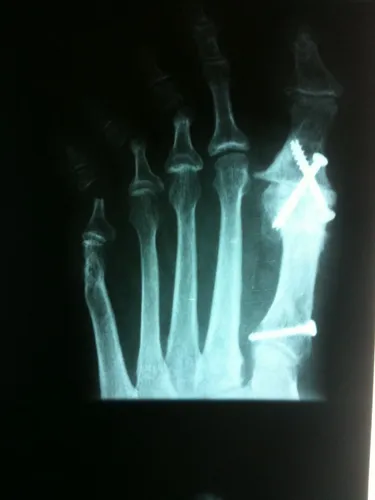

Hallux Varus Pre and Postop with 1st MPJ Fusion Below

Hallux Varus Postop and Preop with 1st MPJ Fusion Below

Deviation of the great toe off of the 1st metatarsal in long standing deformity with history of previous surgery as proof by the surgical screw at the base of the 1st metatarsal. The great toe joint (1st MPJ) is severly degenerated from arthritis (left). Surgical correction of this condition involves fusion of the joint with a cross screw technique (right) which will eliminate pain and difficult with walking and other activities.